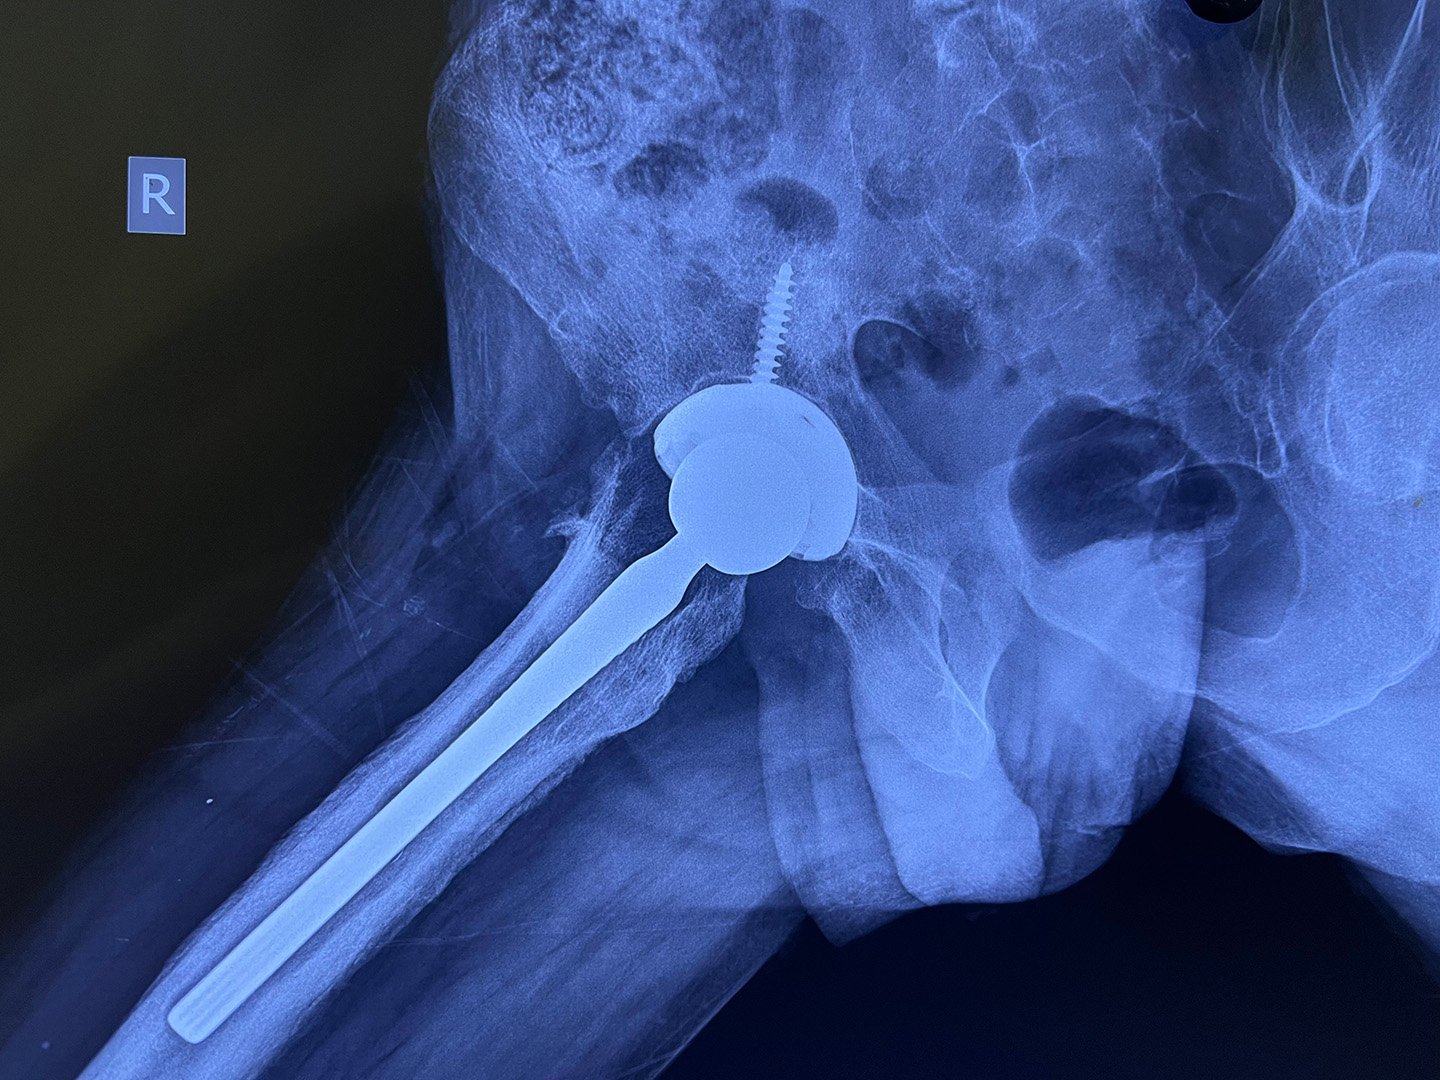

Post-Op - Stage 2 Long Stem THR